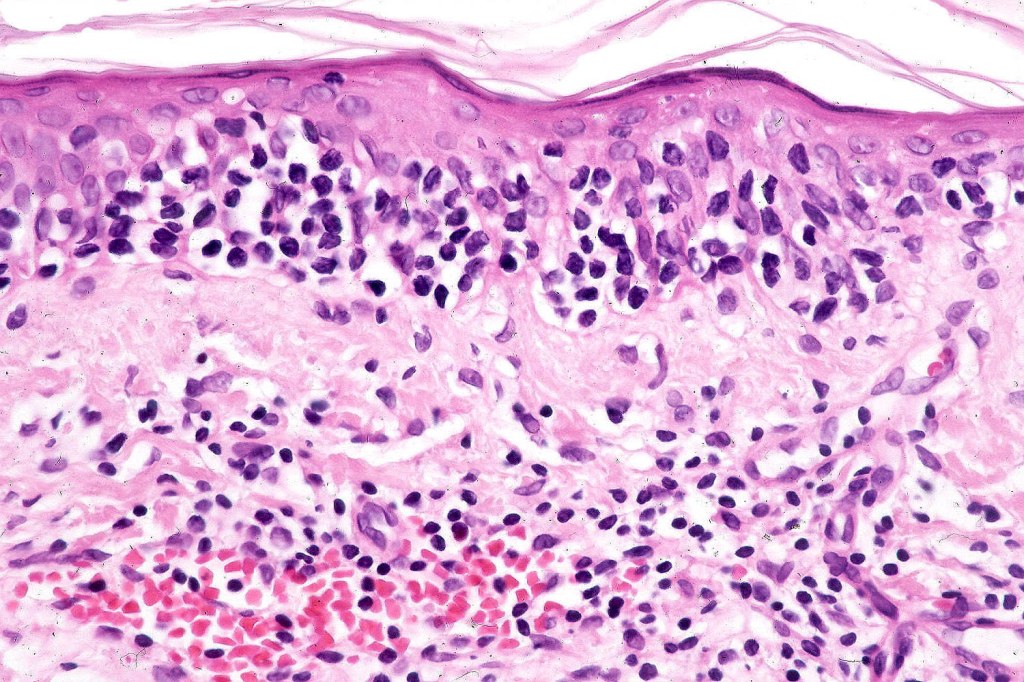

Histological features

The histological hallmark of mycosis fungoides is the presence of large atypical lymphocytes with a convoluted/cerebriform nuclear border (Sézary cells). These may be found at the epidermal-dermal jnuction and as collections within the epidermis (Pautrier microabscess). These are most easily found in plaque stage disease. The epidermal component can be subtle in patch stage disease and is often lost in tumor stage dsease. The classification into patch, plaque & tumor stage disease is less helpful histologically as the features merge from one to the other. It is all a matter of degree.

Patch stage disease

•Changes can be subtle & dependent on clinicopathological correlation; in many patients sequential biopsies over many months may be necessary to establish the diagnosis.

•Mild hyperkeratosis & focal parakeratosis, acanthosis, epidermal atrophy or of normal thickness

•Superficial dermal lymphocytic infiltrate containing variable numbers of Sézary cells with atypical, irregular, hyperchromatic nuclei surrounded by a halo; these can be very few in number and dependant on viewing multiple levels

•Palisading of atypical lymphocytes along the epidermal-dermal border

•Pautrier microabscesses may be present but are often absent in patch stage disease

•Variable interface change with keratinocyte necrosis & pigmentary incontinence

•Eosinophils & plasma cells sometimes present

•Coarse collagen bundles in the papillary dermis can be a feature but this is not as marked as seen in plaque disease

.Although in typical mycosis fungoides fungoides, spongiosis is absent, exceptionally it can be a feature